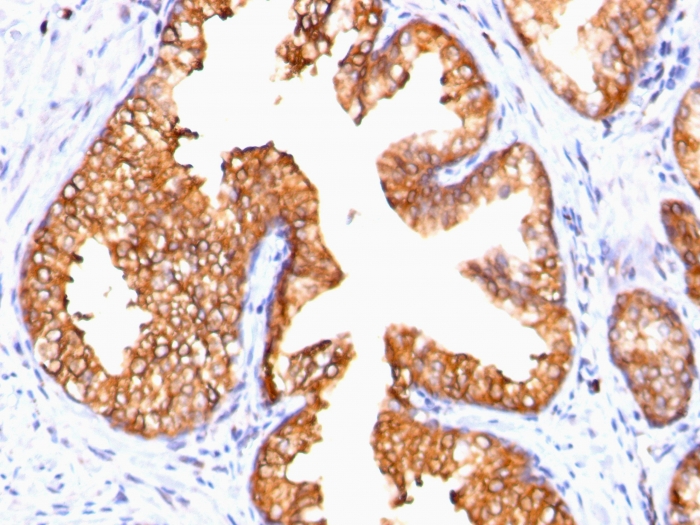

Formalin-fixed, paraffin-embedded human prostate carcinoma stained with ODC-1 Mouse Monoclonal Antibody (ODC1/485).